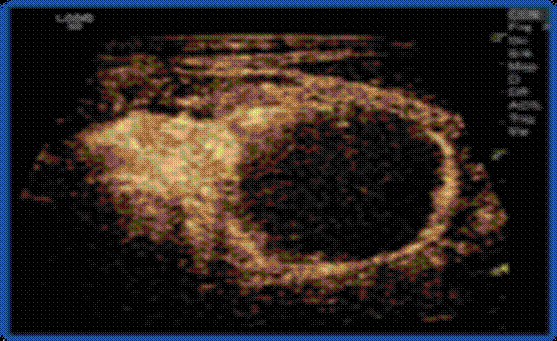

甲状旁腺腺瘤(↑)导致甲旁亢;术前超声造影示血供丰富(↑) ;

术后超声造影提示病灶呈无增强,完全坏死(↑) ;